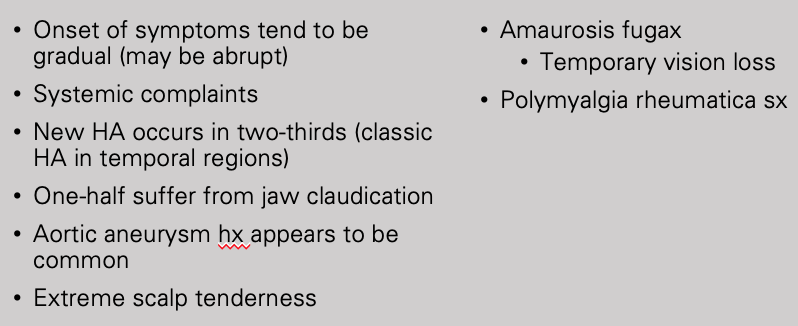

Clinical history Giant Cell (Temporal) Arteritis

Workup for giant cell arthritis